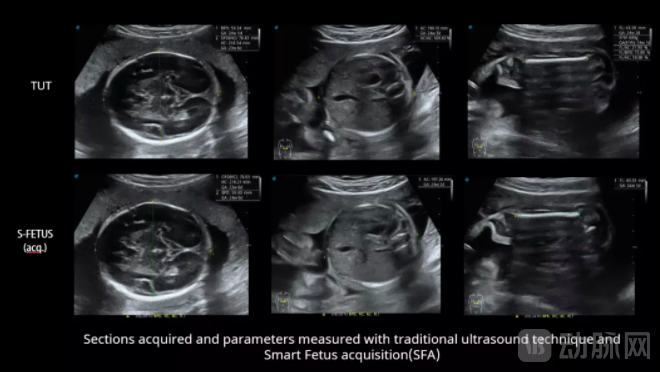

国内某知名医院对比了“凤眼S-Fetus”与传统超声技术在16-41周正常胎儿标准切面获取、切面识别以及自动测量的临床应用。对比结果显示,S-Fetus技术对自动切面获取的成功率可达99%以上,单次切面获取的成功率可达95%以上;生长参数自动测量其准确度可达99%以上,单次测量的准确度可达98%以上。

使用“凤眼S-Fetus”技术进行产科超声诊断(从左到右:采集丘脑横切面、丘脑腹部横切面、股骨纵切面)